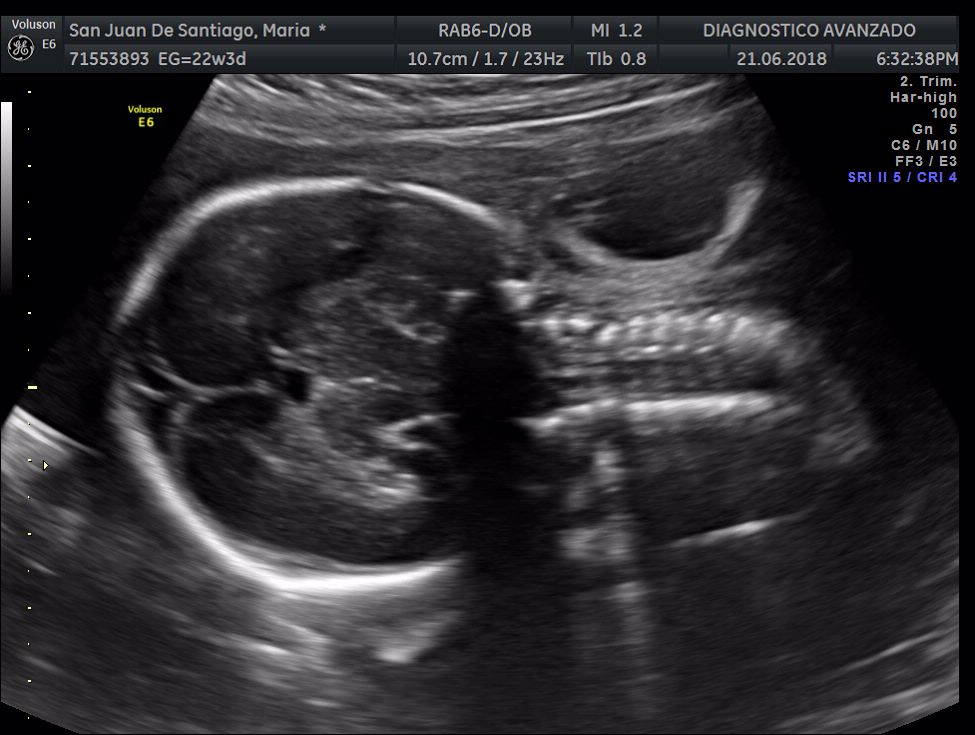

¡Hola a todos! Hoy hemos ido a hacer la tradicional ecografía 3D de la niña, os dejamos todo el material (aunque es un poco demasiado).